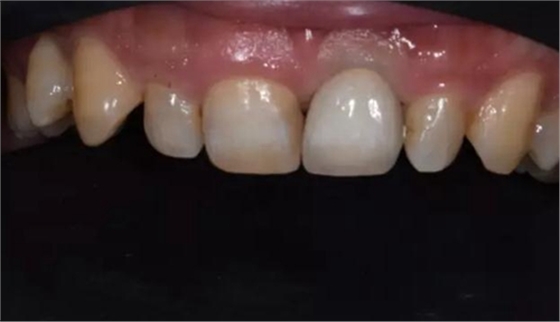

修復體試戴,修復體和原牙顏色上有輕微差異,不過患者本人非常滿意。

修復后正面口內微笑照。